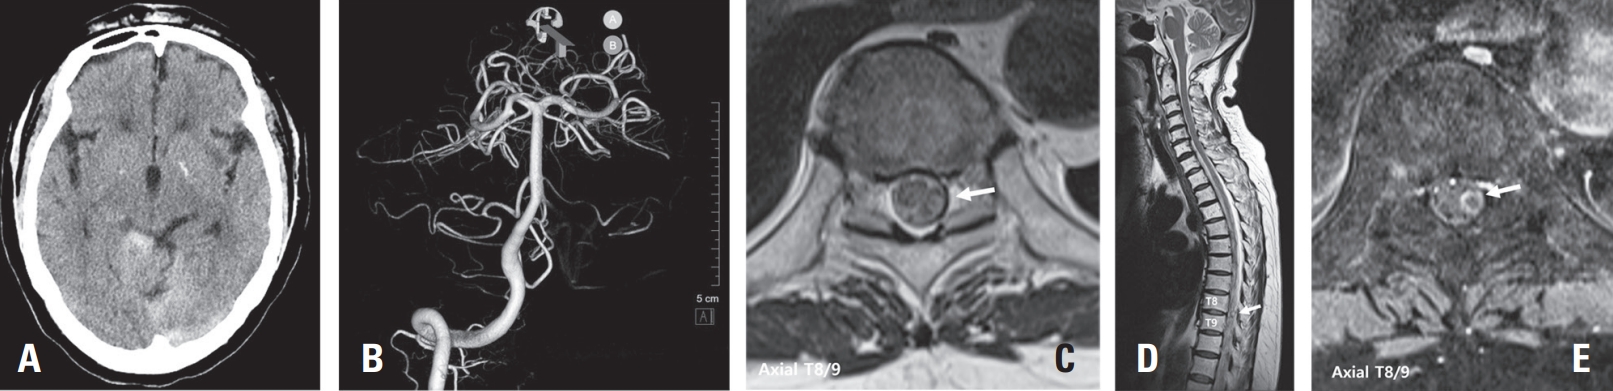

Rupture of Thoracic Radicular Artery Aneurysm Presenting with Subdural Hematoma and Subarachnoid Hemorrhage: Two Case Reports

DOI: https://doi.org/10.63858/jass.15.1.51

Spinal artery aneurysms are exceedingly rare, and their natural history remains poorly understood. Diagnosis can be challenging due to their small size and the difficulty in detection by MR angiography (MRA) or CT angiography (CTA); Digital Subtraction Angiography (DSA) is considered the gold standard diagnostic tool. This case report presents two cases of ruptured thoracic radicular artery aneurysms leading to subdural hematoma (SDH) and subarachnoid hemorrhage (SAH). The first patient, a 71-year-old female, presented with bilateral leg weakness, headache, and severe back pain, where multiple fusiform dilatations of the left T9 radiculopial artery were identified. She showed significant improvement after surgical intervention. The second patient, a 75-year-old female, presented with paraplegia and severe back pain, and a saccular dilatation in the right T10 radiculopial artery was found. She underwent endovascular embolization but showed no neurological improvement. These cases highlight the diverse clinical presentations, diagnostic challenges, and uncertainties in management strategies for ruptured spinal artery aneurysms, emphasizing the need for prompt intervention, especially in cases with significant or progressive neurological deficits.